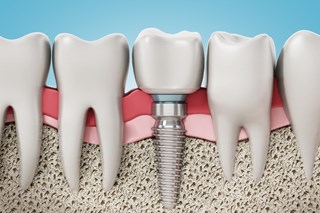

Vi riktar oss främst till vuxna patienter och erbjuder all typ av allmäntandvård såsom undersökningar, lagningar, kronor/broar, tandutdragningar och tandreglering. Vi erbjuder även estetisk tandvård och hjälp att ersätta saknade tänder. Hos oss får du hjälp från första undersökningen till det färdiga behandlingsresultatet, oavsett om du kommer med ett stort eller litet behandlingsbehov.